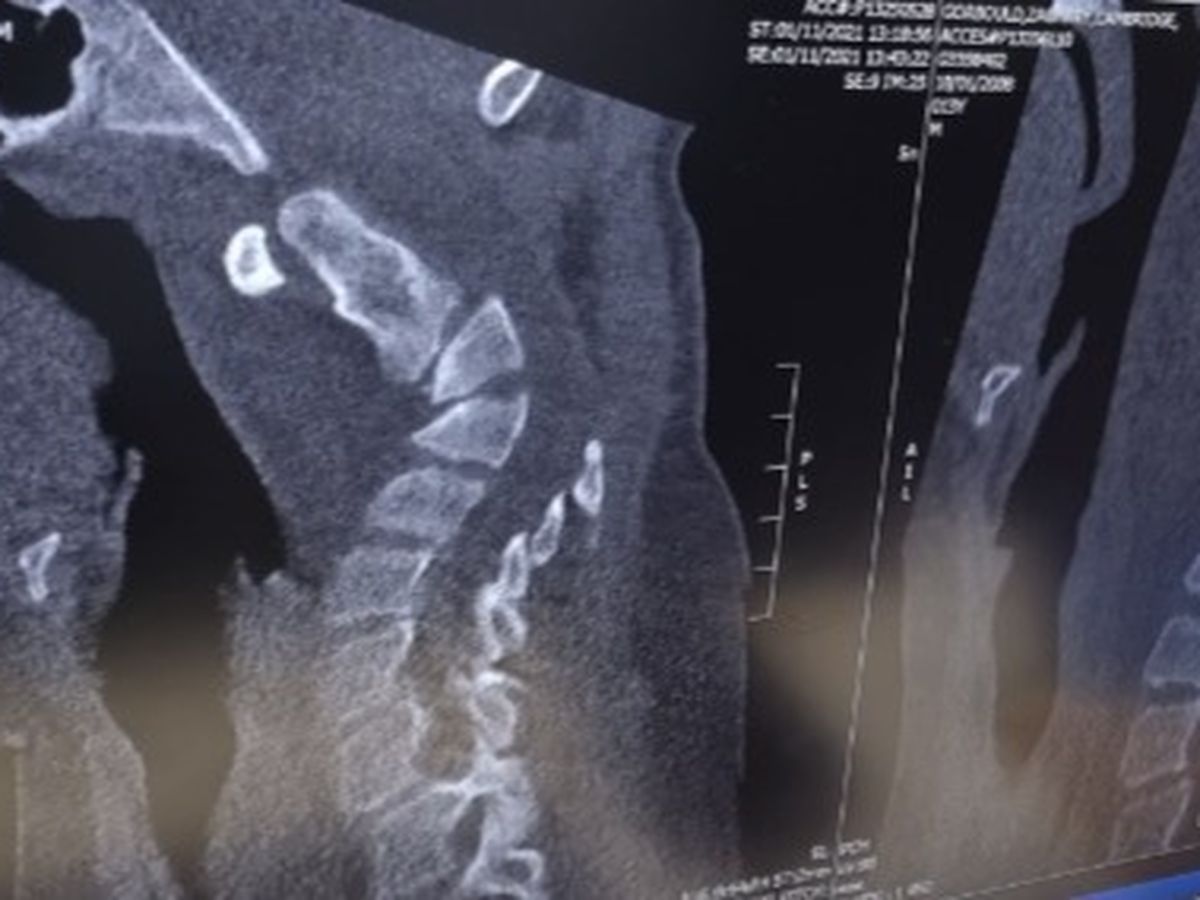

Left side MRI taken 08.09.2021 / Right side MRI taken 02.03.2021

Unfortunately in November, Zachary's mobility declined. He is a severe fall risk as he is very top heavy with his chin slipping back to his chest as his soft collar has not refrained falling of his head. The attached MRI shows the difference of six months between slight cervical muscle deterioration (March 2021) and a major cervical muscle and bone deterioration - Kyphosis (September 2021). Thursday 11th November 2021, Zachary attended a scheduled Neurosurgery appointment. Dr Saha (PCH - Neurosurgery Consultant) was very concerned with the deterioration of Zac's mobility and cervical spine alignment. She called Dr Derrick (currently on long service leave - Rasopathy PCH) to discuss an emergency admission as the vital signs of the complexity within the spinal cord and ongoing mobility issues were of immediate discussions that could not be achieved in outpatient status as the timing is of great importance to the ongoing health and overall wellbeing of Zachary and his family. 5pm Thursday evening, Zachary was admitted to Ward 1B under a complexity team involving Neurosurgery, Rasopathy and Orthopaedics.